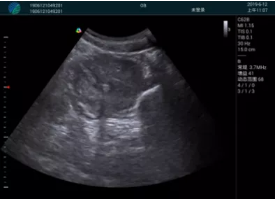

頸動(dòng)脈血流充盈飽滿,無外溢

肝內(nèi)血管顯示清晰,血流敏感無外溢